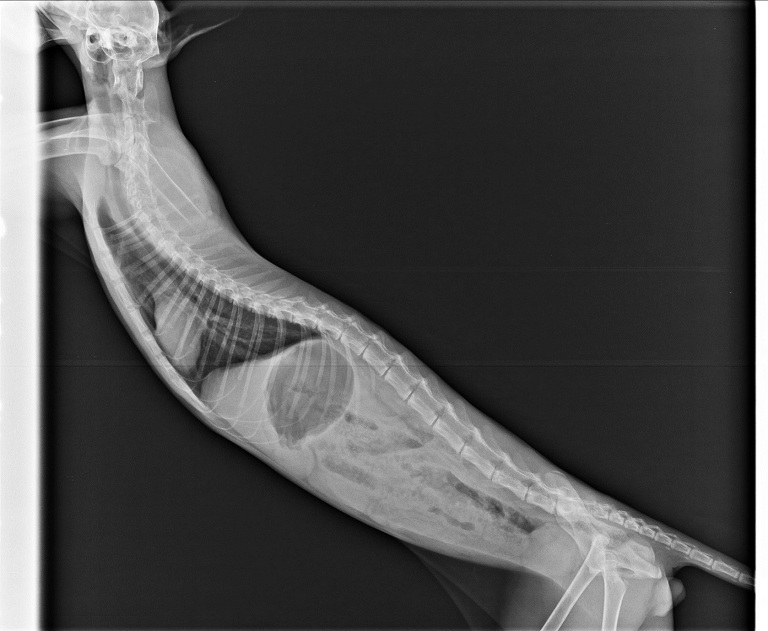

小賓在住院期間做了3次的血檢及X光照檢查,

另外也對小賓的食物選擇性作了一些嘗試,

因而更瞭解該如何做出相應的改善來幫助小賓,